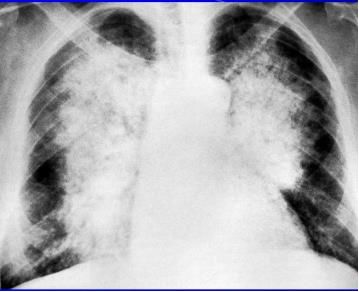

再来一个更直白的蝶翼征,几乎可以翩翩起舞了。

另外,肺水肿还可以出现肺纹理的改变:以前肺纹理少的地方,肺纹理增多;以前肺纹理相对多的地方,肺纹理更多,或者反而减少。